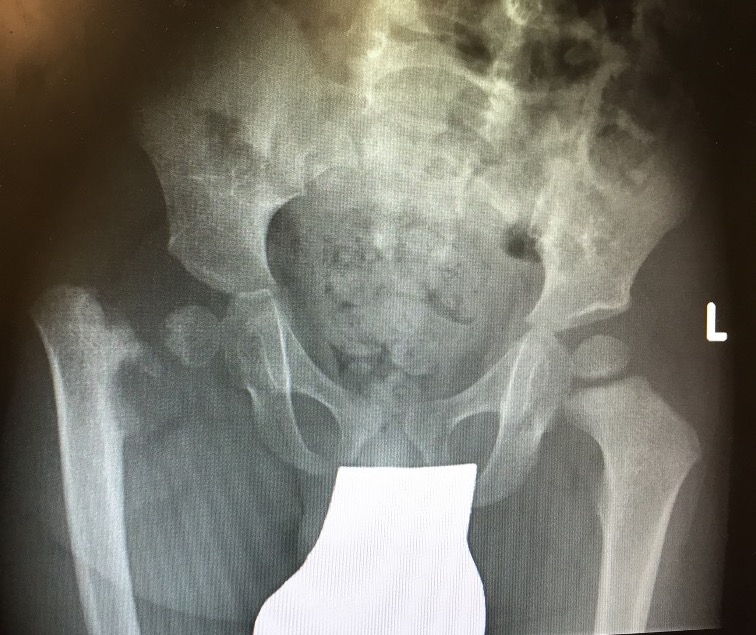

Class C

- no femoral head

- acetabulum severe dysplastic

- very short femoral shaft with bony tuft proximally

Class D

- femoral head & acetabulum completely absent

- femur consists of condyles only

Class C & D

No femoral heads

Stabilise hip

- pelvic support osteotomy

- osteotomy proximal femur

- supported by ischium

- distal osteotomy for mechanical axis